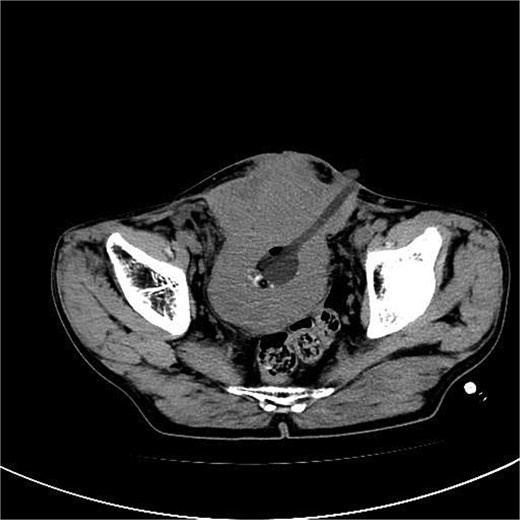

A 53-year-old male, presented to a local hospital in April 2021 due to lower back discomfort. There was no weight loss, fatigue, fever, or other systemic symptoms. Urinalysis showed leukocytes (+++); computed tomography (CT) revealed a 76 × 74 mm stone, bladder wall thickening, and dilation of the bilateral renal pelvis and ureters (Fig. 1). Subsequently, he underwent pubic bladder incision for stone removal and bladder diversion at that hospital. Postoperatively, the incision site was swollen, exuding fluid, and did not heal over an extended period. A total of 14 months after the initial surgery, he was admitted to our hospital. On examination, there was excessive granulation tissue proliferation around the bladder incision wound and near the bladder diversion tube, with surface exudation and easy bleeding upon touch (Fig. 2). Upon admission, urinalysis showed leukocytes (++), occult blood (++), glucose (++), and protein (++). Postprandial blood glucose level was 19.58 mmol/l. Urine culture indicated tropical pseudo-filamentous yeast and Enterococcus. Secretion culture showed E. coli and Klebsiella pneumoniae subsp. Blood routine test indicated white blood cell count and highly sensitive C-reactive protein within normal ranges. He received infection control, glucose management, and wound care, but the wound did not heal. Abdominal CT and pelvic magnetic resonance imaging (MRI) revealed bladder wall thickening and soft tissue in the anterior pelvic area (Fig. 3). Histopathological results from abdominal wall tissue biopsy indicated moderately differentiated squamous cell carcinoma. Immunohistochemistry indicated: CK(pan)(+), CK20(−), CK7(−), PAX-8(−), GATA3(−), P63(+), P53(+), Ki-67(+) at 40% (Fig. 4).

Abdominal CT and pelvic MRI revealed bladder wall thickening and soft tissue in the anterior pelvic area.